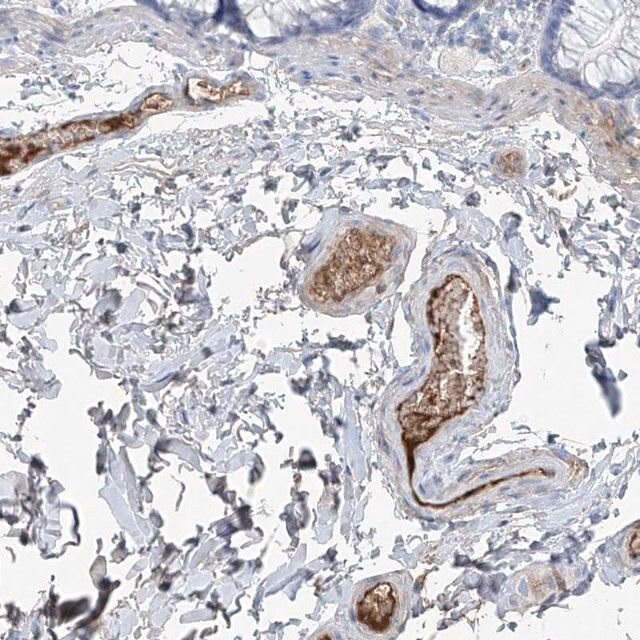

The gene programmed cell death-5 (PDCD5) is mapped to human chromosome 19q13.11. The protein is mainly localized in the plasma membrane and the cytoplasm. However, under certain biological conditions PDCD5 relocalizes to the nucleus.

The Human Protein Atlas project can be subdivided into three efforts: Human Tissue Atlas, Cancer Atlas, and Human Cell Atlas. The antibodies that have been generated in support of the Tissue and Cancer Atlas projects have been tested by immunohistochemistry against hundreds of normal and disease tissues and through the recent efforts of the Human Cell Atlas project, many have been characterized by immunofluorescence to map the human proteome not only at the tissue level but now at the subcellular level. These images and the collection of this vast data set can be viewed on the Human Protein Atlas (HPA) site by clicking on the Image Gallery link. To view these protocols and other useful information about Prestige Antibodies and the HPA, visit sigma.com/prestige.

YY1-associated factor 2 (YAF2) binds and stabilizes programmed cell death-5 (PDCD5), thereby promoting TP53 (Tumor suppressor p53)-mediated apoptosis. In lung A549 cancer cells, DNAJB1 (DnaJ homolog subfamily B member 1) binds and degrades PDCD5 to suppress p53-dependent apoptosis of cancer cells. PDCD5 stimulates promoter activity of KLF9 (Krueppel-like factor 9). Up-regulation of KLF9 inhibits cell proliferation and induces apoptosis in hepatocellular carcinoma cells. PDCD5 is down-regulated in ovarian cancer cells. Absence of PDCD5 is correlated with disease progression and stage in ovarian cancer.